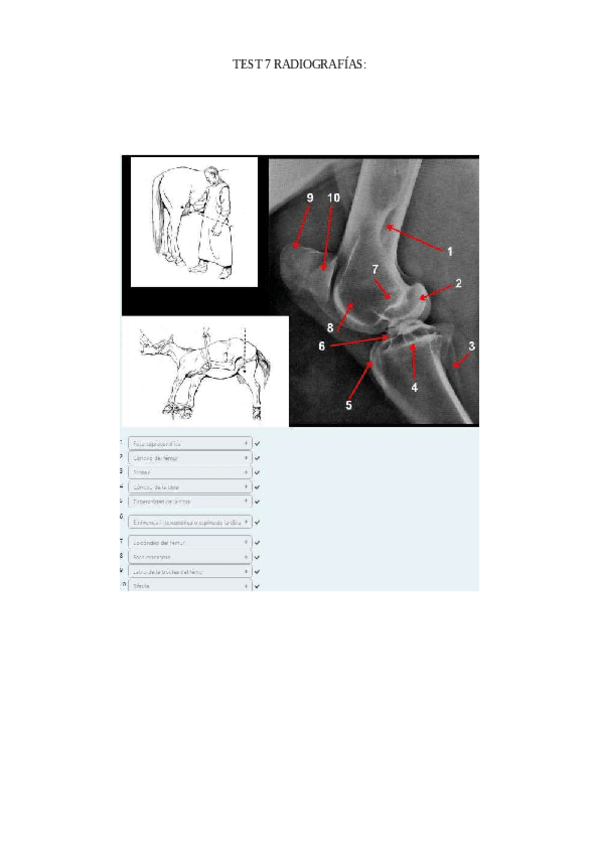

He publicado nuevos apuntes de 1º EMBRIOLOGÍA Y ANATOMÍA I: TEST-7-radiografias-corregido.pdf

7 páginas